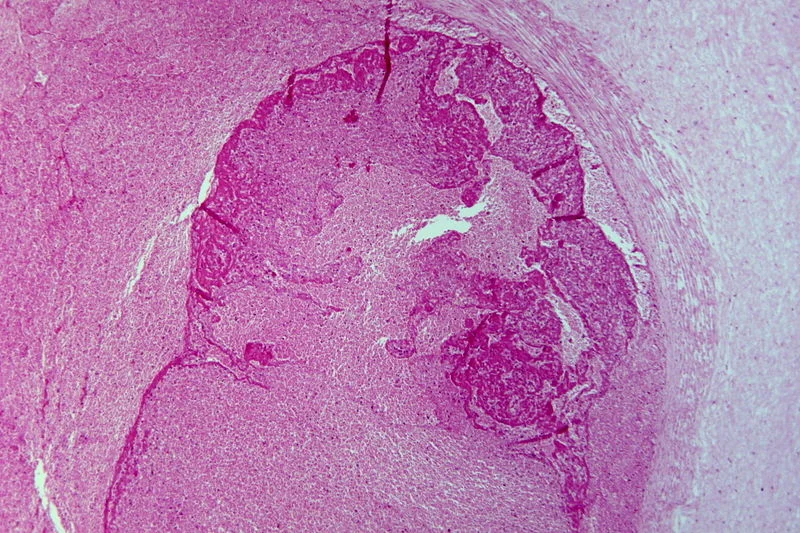

Umbilical vein thrombosis